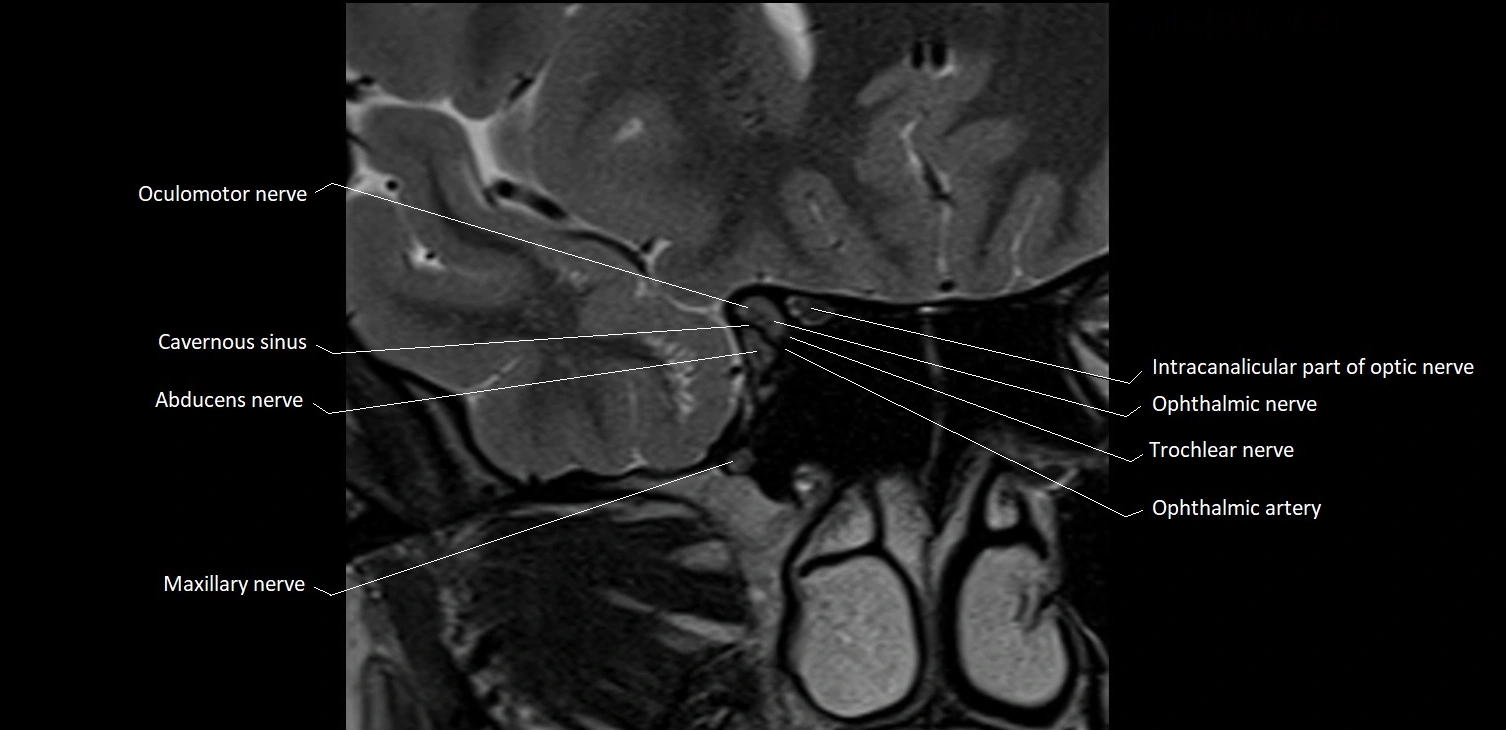

- Abducens nerve (Cranial nerve VI)

- Intracanalicular part of optic nerve

- Maxillary nerve

- Medial canthal ligament

- Oculomotor Nerve (Cranial Nerve III)

- Trochlear nerve (Cranial nerve IV)